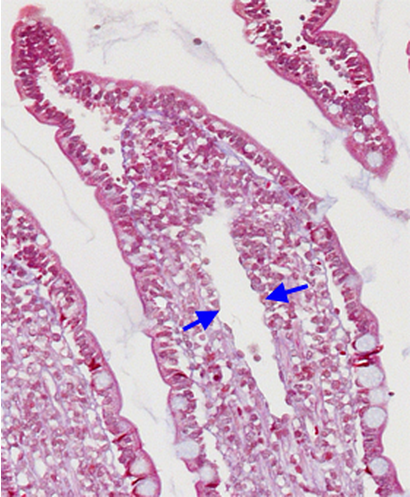

margins of a lacteal within a villus